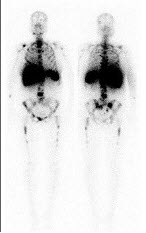

男,47岁,进行性消瘦贫血,全身疼痛1年。行全身骨显像如图,可能的诊断是()

一患者的99Tcm-RBC门控心血池显像时相分析如图,诊断是()

A.左心室前壁缺血

B.扩张型心肌病

C.心尖室壁瘤形成

D.左心室传导异常

E.以上都不是